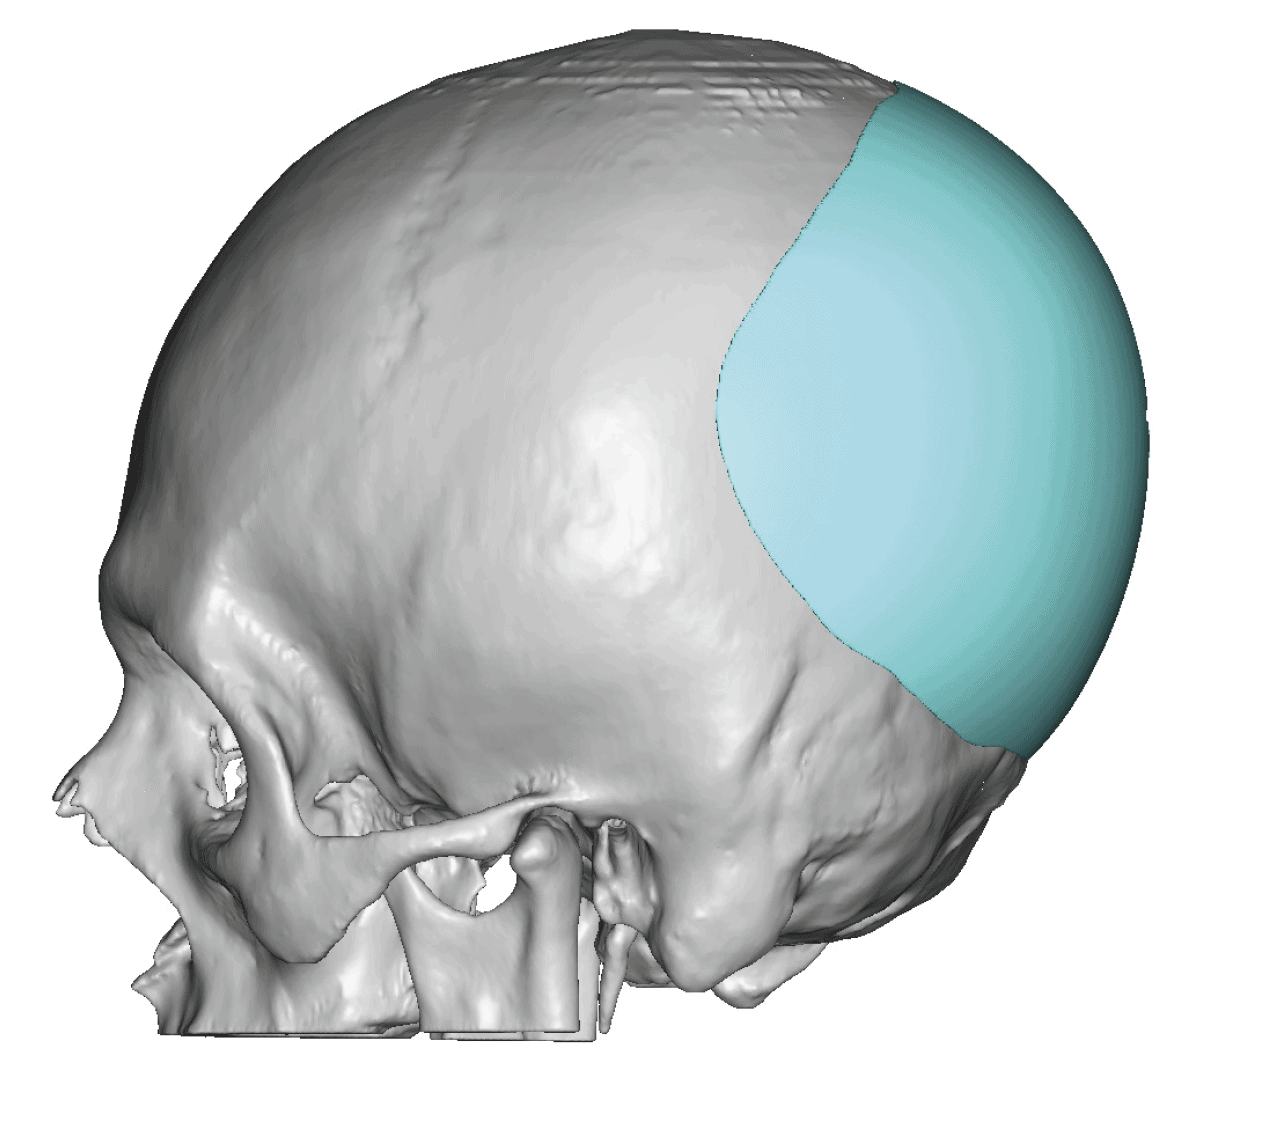

Patient 49

Desire for further skull augmentation after a primary skull implant.

Five years after an initial custom skull implant placement a new custom skull implant that increased the volume by 35% was placed.

Desire for further skull augmentation after a primary skull implant.

Five years after an initial custom skull implant placement a new custom skull implant that increased the volume by 35% was placed.